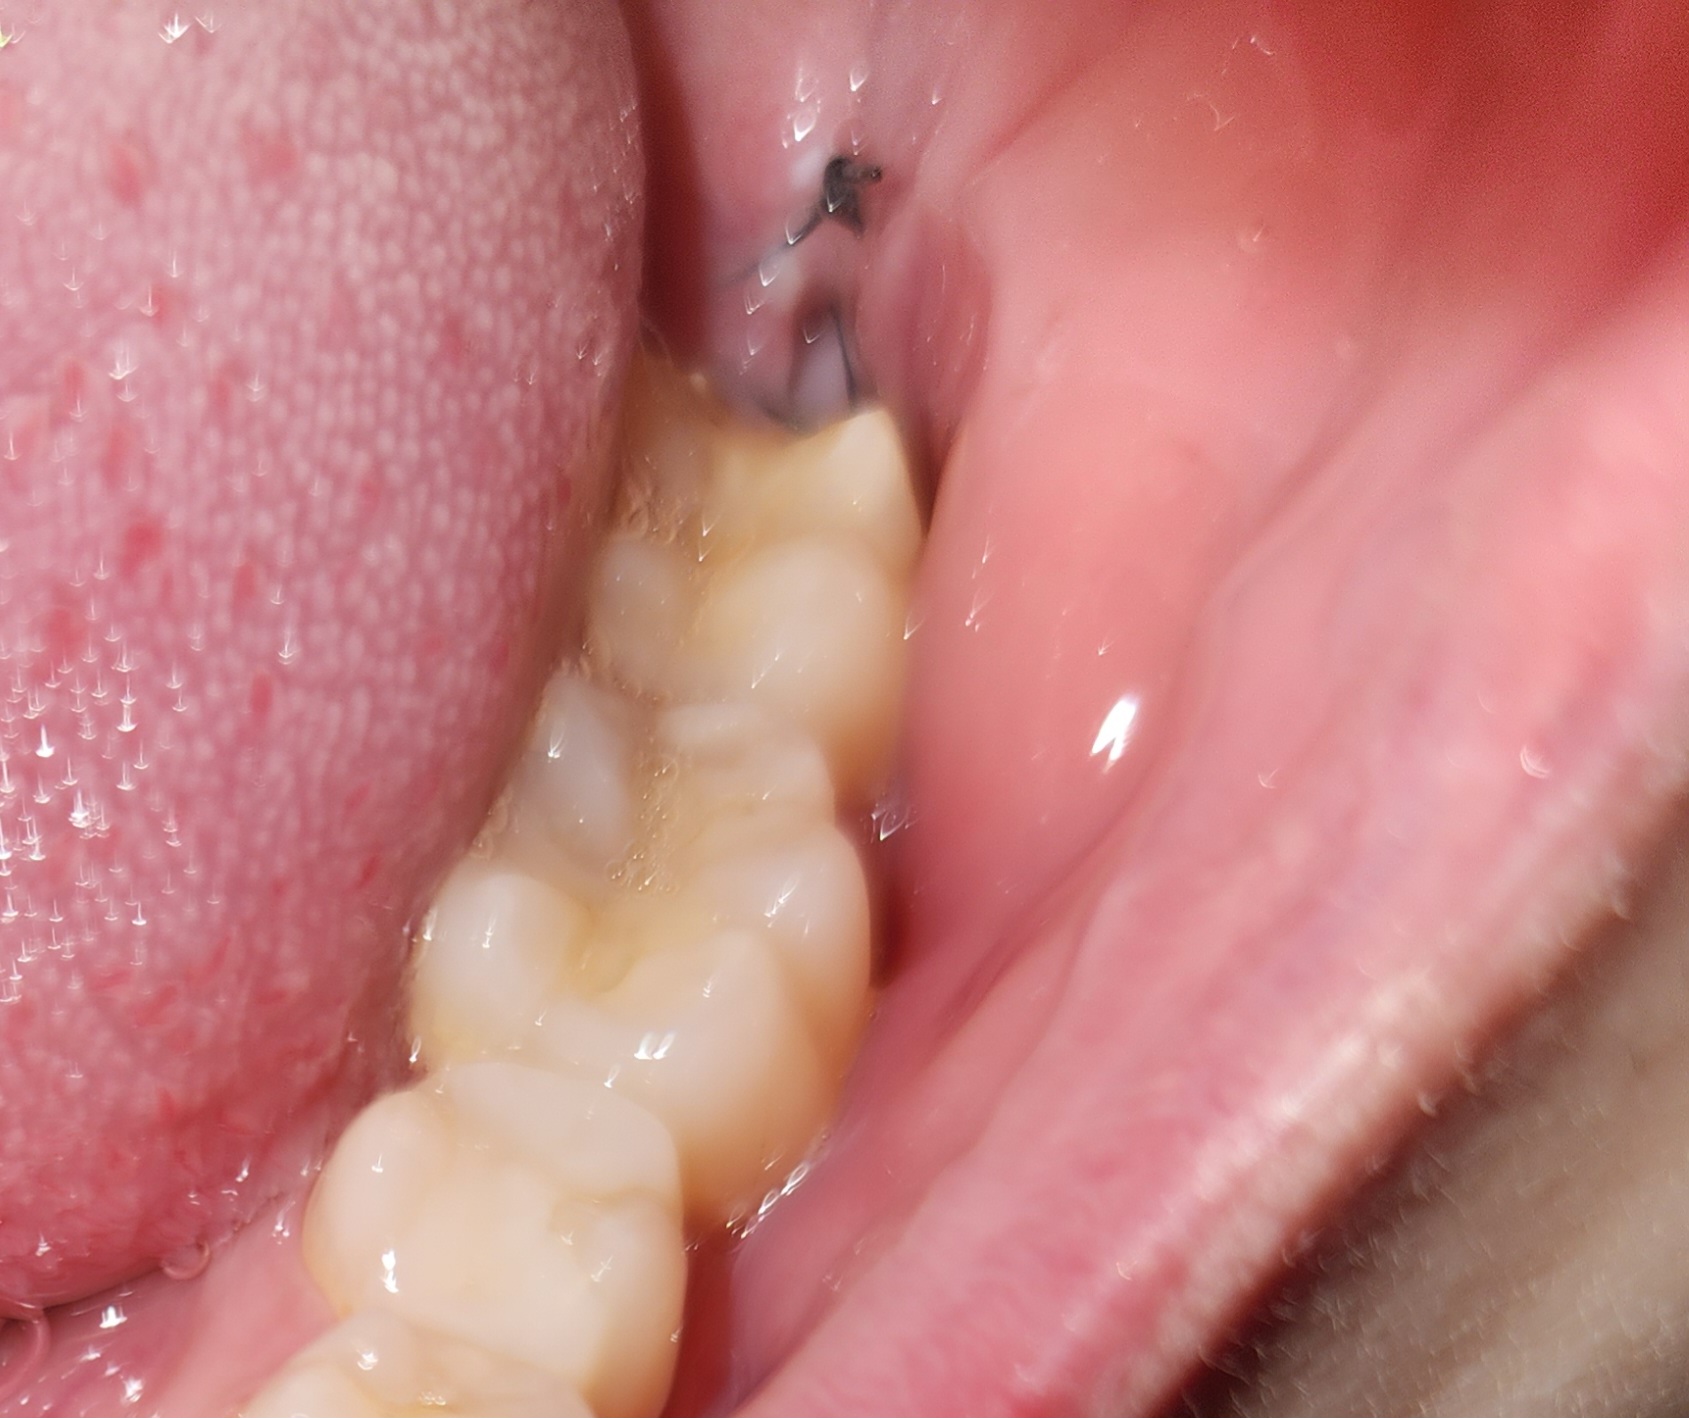

親知らず抜歯から4日後、ムズムズ、ズキズキした痛みがあります。ドライソケットですか?

4日前に左下の親知らずを抜きました。

歯根が骨を抱え込んでいるような形をしていたらしく、かなり難渋したと担当医より言われました。

半分埋もれていたため切開して、歯を割って抜きました。

終了後、ガーゼを40分程度噛んで捨てました。

その時から血餅は目に見えず、写真のように穴がぽっかりと開いたような形でした。